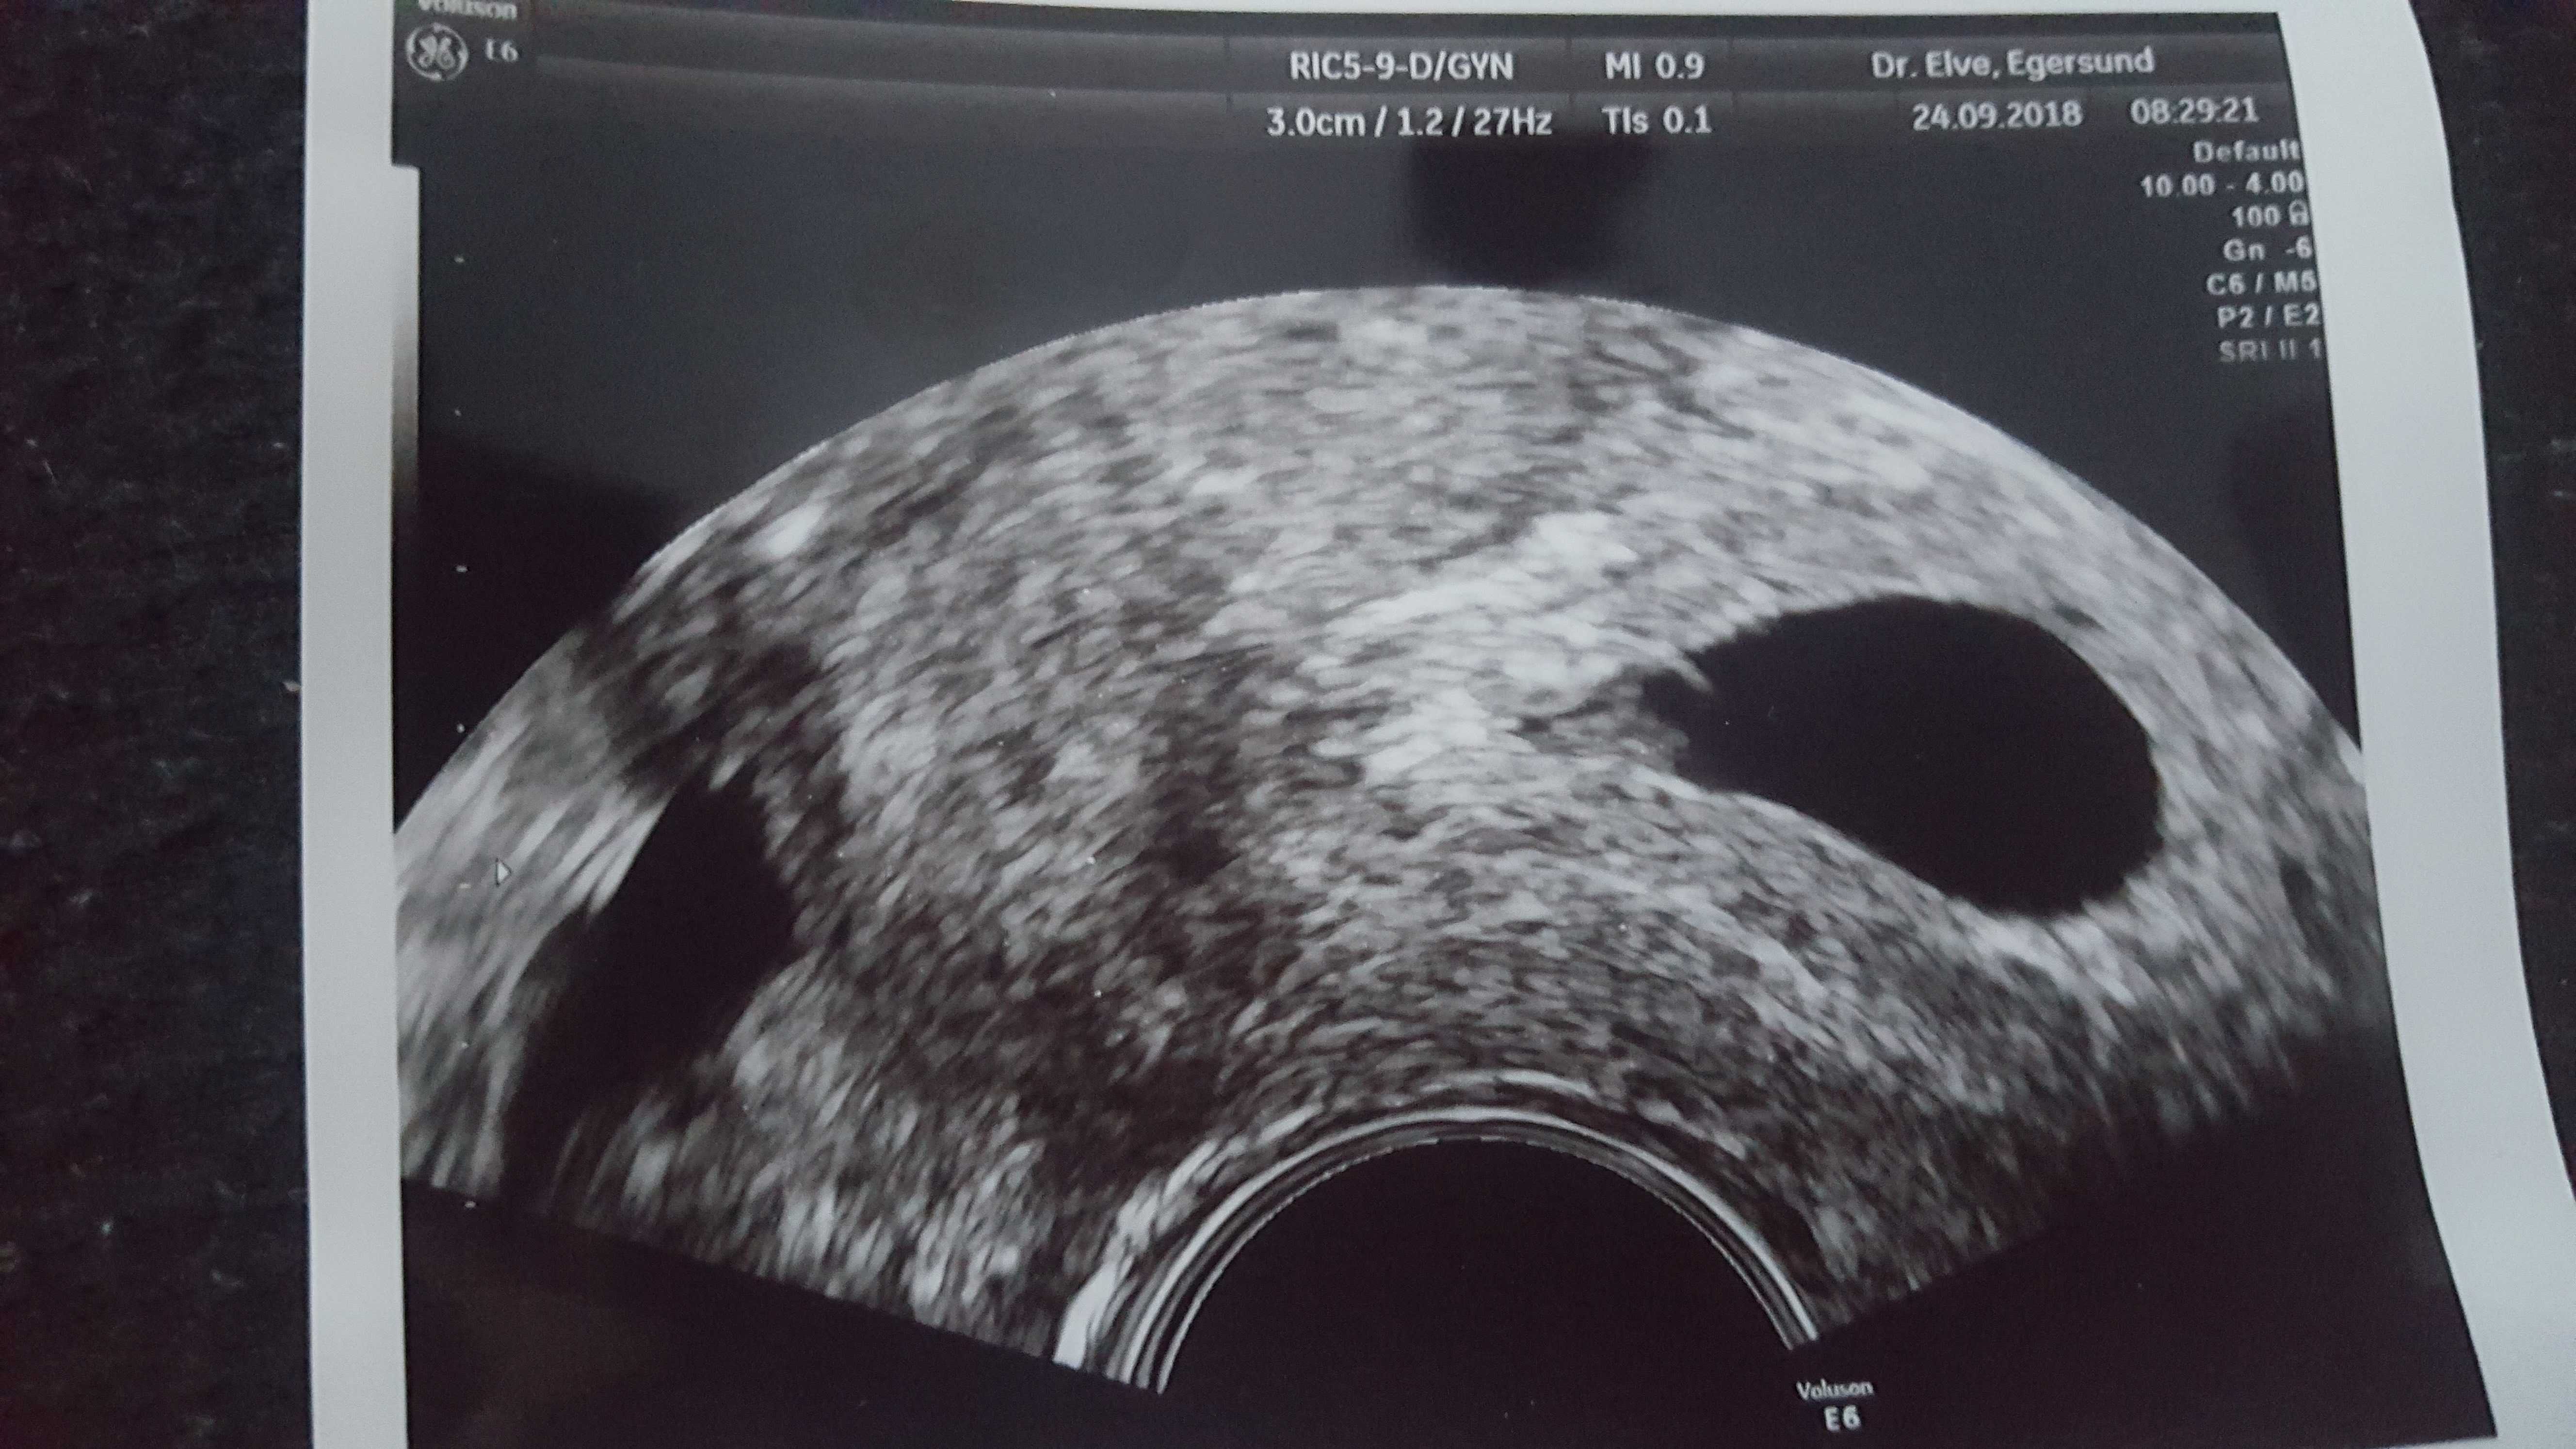

Gratuluję [emoji7][emoji7][emoji7][emoji7]Mamy serduszko [emoji173]Zobacz załącznik 901169